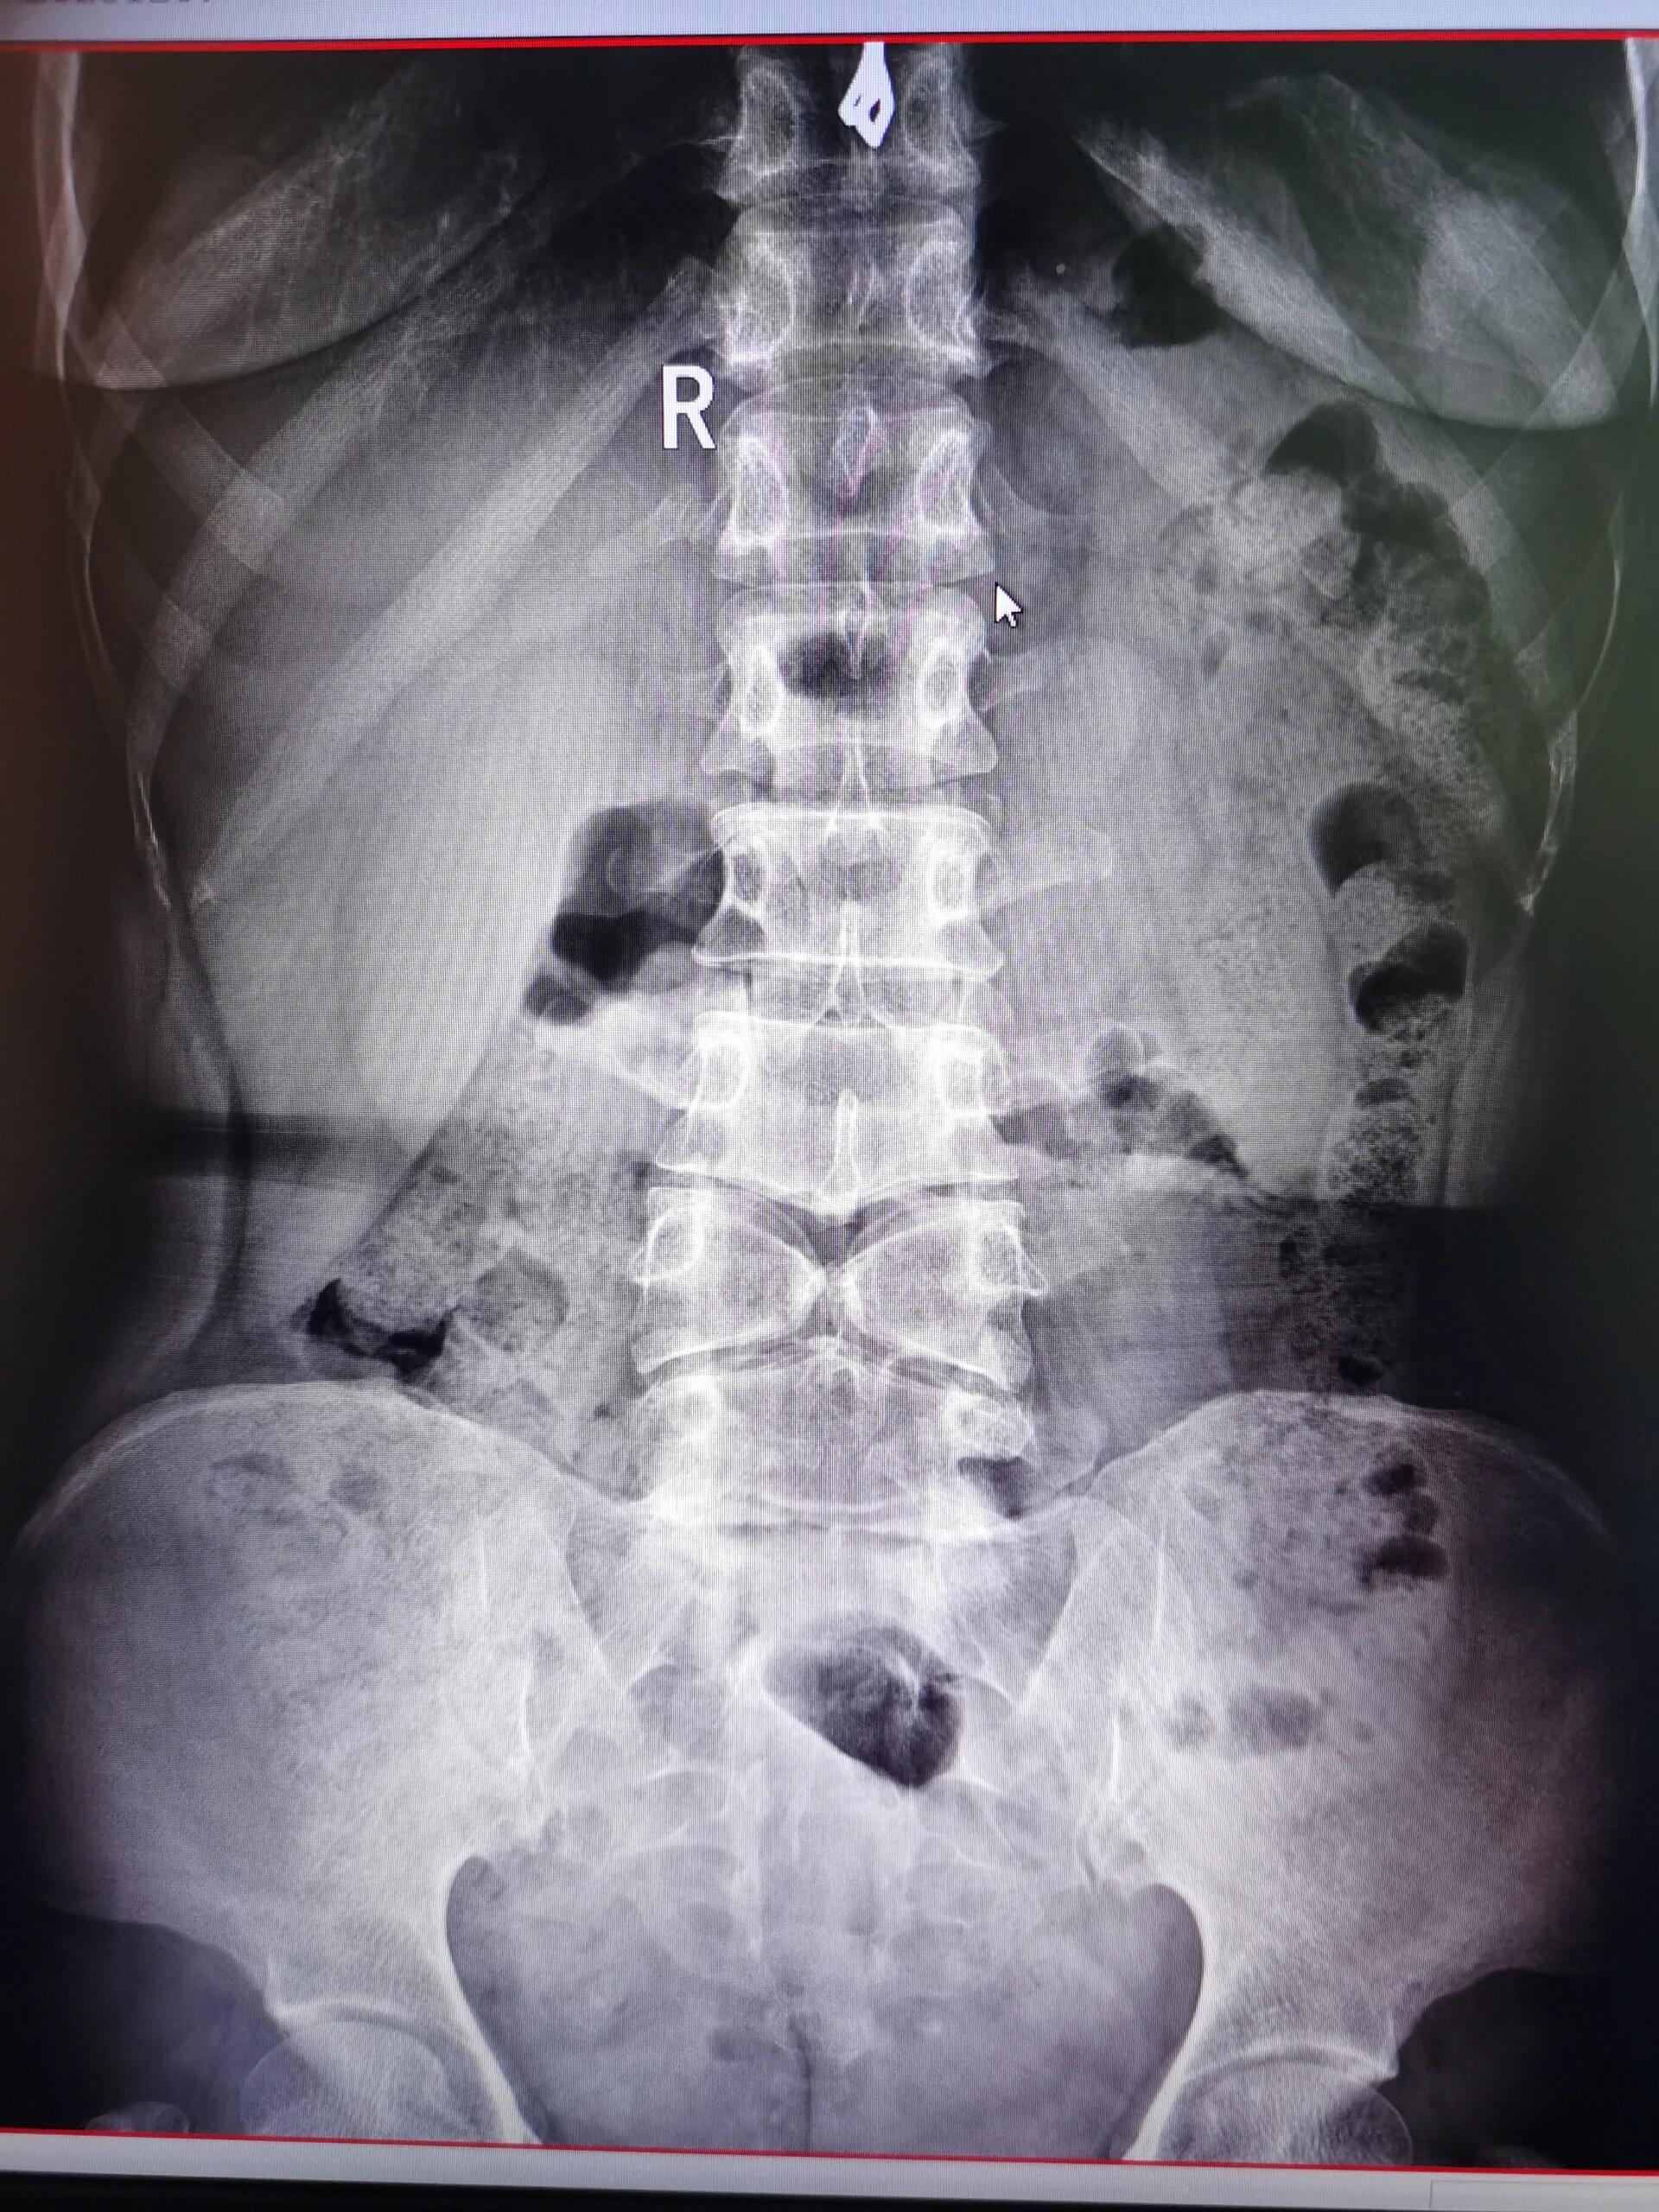

腰椎蝴蝶椎

图片尺寸1920x2560

细一看,有问题!胎儿腰椎和部分胸椎椎体有纵向裂开,考虑蝴蝶椎.

图片尺寸1080x810